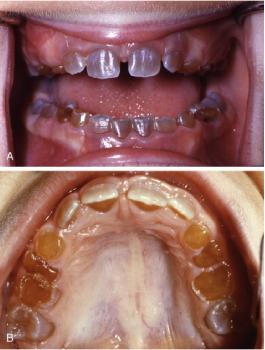

Image Observations: The picture shows the front teeth with small, dark, punctate (dot-like) spots or specks, primarily located close to the gum line (gingival margin). The spots are circled in red for emphasis. The surrounding gum tissue (gingiva) appears generally pink and healthy in the visible area.

Client Statement: "Had it some days now. Can't remove with brush."

The dark spots you are describing and that are visible in the image could be one of several things. Since you cannot remove them with a brush, they are likely not simple surface stains.

| 1. Enamel Hypoplasia (Arrested Defect) | These are localized defects in the formation of the enamel, often appearing as small pits or grooves that can accumulate dark stains over time. They are developmental and not actively spreading. | Low Risk. Primarily an aesthetic issue. Could become a focus for decay if the pits are deep and not properly sealed/cleaned. |

| 2. Non-Carious/Early Carious Lesions (Early Decay) | Small areas of demineralization or early decay that have arrested (stopped progressing) and picked up dark stains from food/drink. They may be small cavities (caries) that have not progressed deeply yet. | Moderate Risk. If the area is active decay, it will progress deeper into the dentin, causing sensitivity and eventually a large cavity or pulp infection. |

| 3. Extrinsic Staining (Tetracycline, Fluorosis, Iron) | Certain medications (like Tetracycline taken during development), excessive fluoride intake (Fluorosis), or supplements (iron) can cause intrinsic or heavily embedded extrinsic stains that are dark and hard to remove. | Low Risk. Primarily aesthetic. Does not directly threaten the tooth's structure, but diagnosis is important. |

| 4. Dental Calculus/Tartar | Hardened plaque that has calcified and stained darkly. Usually bulkier, but small, stained deposits near the gum line are common. | Moderate Risk. Calculus cannot be brushed off. It harbors bacteria, leading to gingivitis (gum inflammation) and eventually periodontitis (bone loss). |